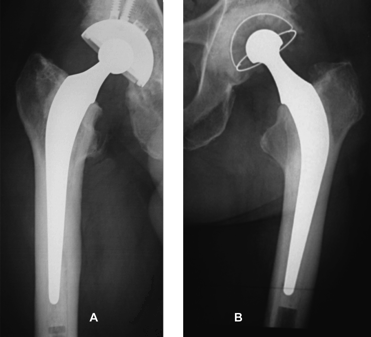

and a QUATTRO® cementless dual mobility cup (groupe Lépine â Genay â France), always with HA coating, for patients over 70 years of age, as well as in the case of patients with fractures of the femoral neck, neurological diseases or cognitive impairment (Figure 2).

Figure 2: X-ray of HA cementless dual mobility cup